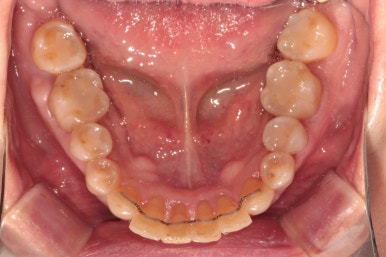

이제 정말 많이 배열이 완성되었습니다. 아래 앞니를 배열시키느라 시간이 조금 더 걸렸던 것 같아요.

대망의 교정치료 완성의 날.

교정치료가 완성되었습니다!!

비록 앞니가 깨진 것이 조금 눈에 띄긴 하지만... 환자분은 배열만 해도 매우 만족한다 하셔서 이렇게 치료를 마무리 하였습니다. 끝까지 배열이 어려웠던 아래 앞니의 가지런함이 눈에 띕니다.

교합평면도 평평하게 조화롭게 완성된 것을 보실 수 있습니다.

생각보다 평평한 교합평면을 달성해내는 것은 어려운 과정입니다.

씹는면에서 보아도 상당히 가지런히 완성된 것을 보실 수 있습니다.

교정치료가 끝나면 혀쪽에 유지장치를 붙여드리는데요, 치석이 보다 덜 생기도록 하기 위해서 치아 표면 그대로의 모양을 따라가는 와이어를 제작하여 부착해드리고 있습니다.

조금 더 비용을 들이더라도 정성담긴 모양의 유지장치입니다!!

치아 사이 공간까지도 완벽하게 밀착하고 지나가야 좋은 고정식 유지장치입니다. 그래야 치석도 덜 생기고 관리가 편해지시거든요..

교정유지장치 끊어짐 없이 아주 깔끔하게 잘 관리되고 있습니다.

조금 힘드셨겠지만, 철저한 구강위생보조용품 사용으로 더욱 완벽히 관리해주시고 있는 모습입니다.